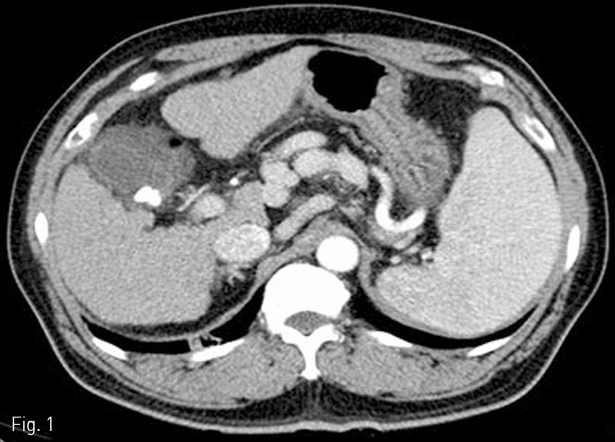

5 Fr Yashiro catheter (Terumo, Tokyo, Japan)를 복강동맥을 통해 비장동맥에 삽입한 후 혈관조영술을 시행하여 비장동맥의 분지들을 먼저 확인하였다 (Fig. 2). 0.021 inch guide wire (GT guide wire; Terumo)와 2.7 Fr microcatheter (Progreat; Terumo, Tokyo, Japan)를 이용하여 co-axial technique으로 middle segmental artery가 분지된 이후 splenic hilum에서의 비장동맥에 12mm×3cm 1개, 10mm×3cm 3개의 platinum coils (IDC: Interlocking Detachable Coil; Boston Scientific, Tokyo, Japan)와 gelfoam (Cutanplast, Mascia Brunelli Spa, Milano, Italy), N-butyl cyanoacrylate (NBCA; Histoacryl; B.Braun, Melsungen, Germany)와 Lipiodol (Guerbet, Paris, France) 1:4 혼합물을 이용하여 superior, inferior segmental artery를 색전하였다 (Fig. 3). 색전 후 비장동맥 조영술에서 splenic hilum level에서 원위부 색전이 이루어진 것을 확인하였다(Fig. 4).

Fig 4

Completion angiogram demonstrates occlusion of the distal branches of splenic artery at the hilum.